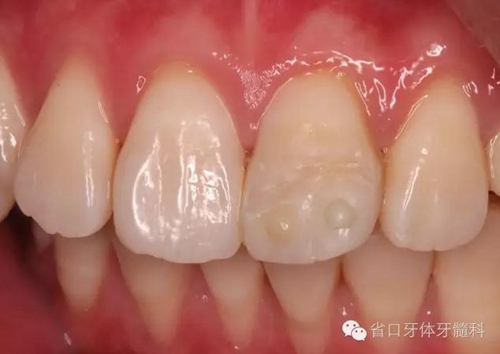

口內(nèi)檢查:21切1/3-1/2折斷,髓腔暴露,探痛明顯

近中鄰面探及齲損,松-,叩+,齦緣輕度紅腫,探及齦下結(jié)石。

術(shù)前口內(nèi)照

折斷之牙體嚴(yán)重脫水,呈白堊色,斷端對(duì)位后吻合度較好,僅少許牙體缺損。